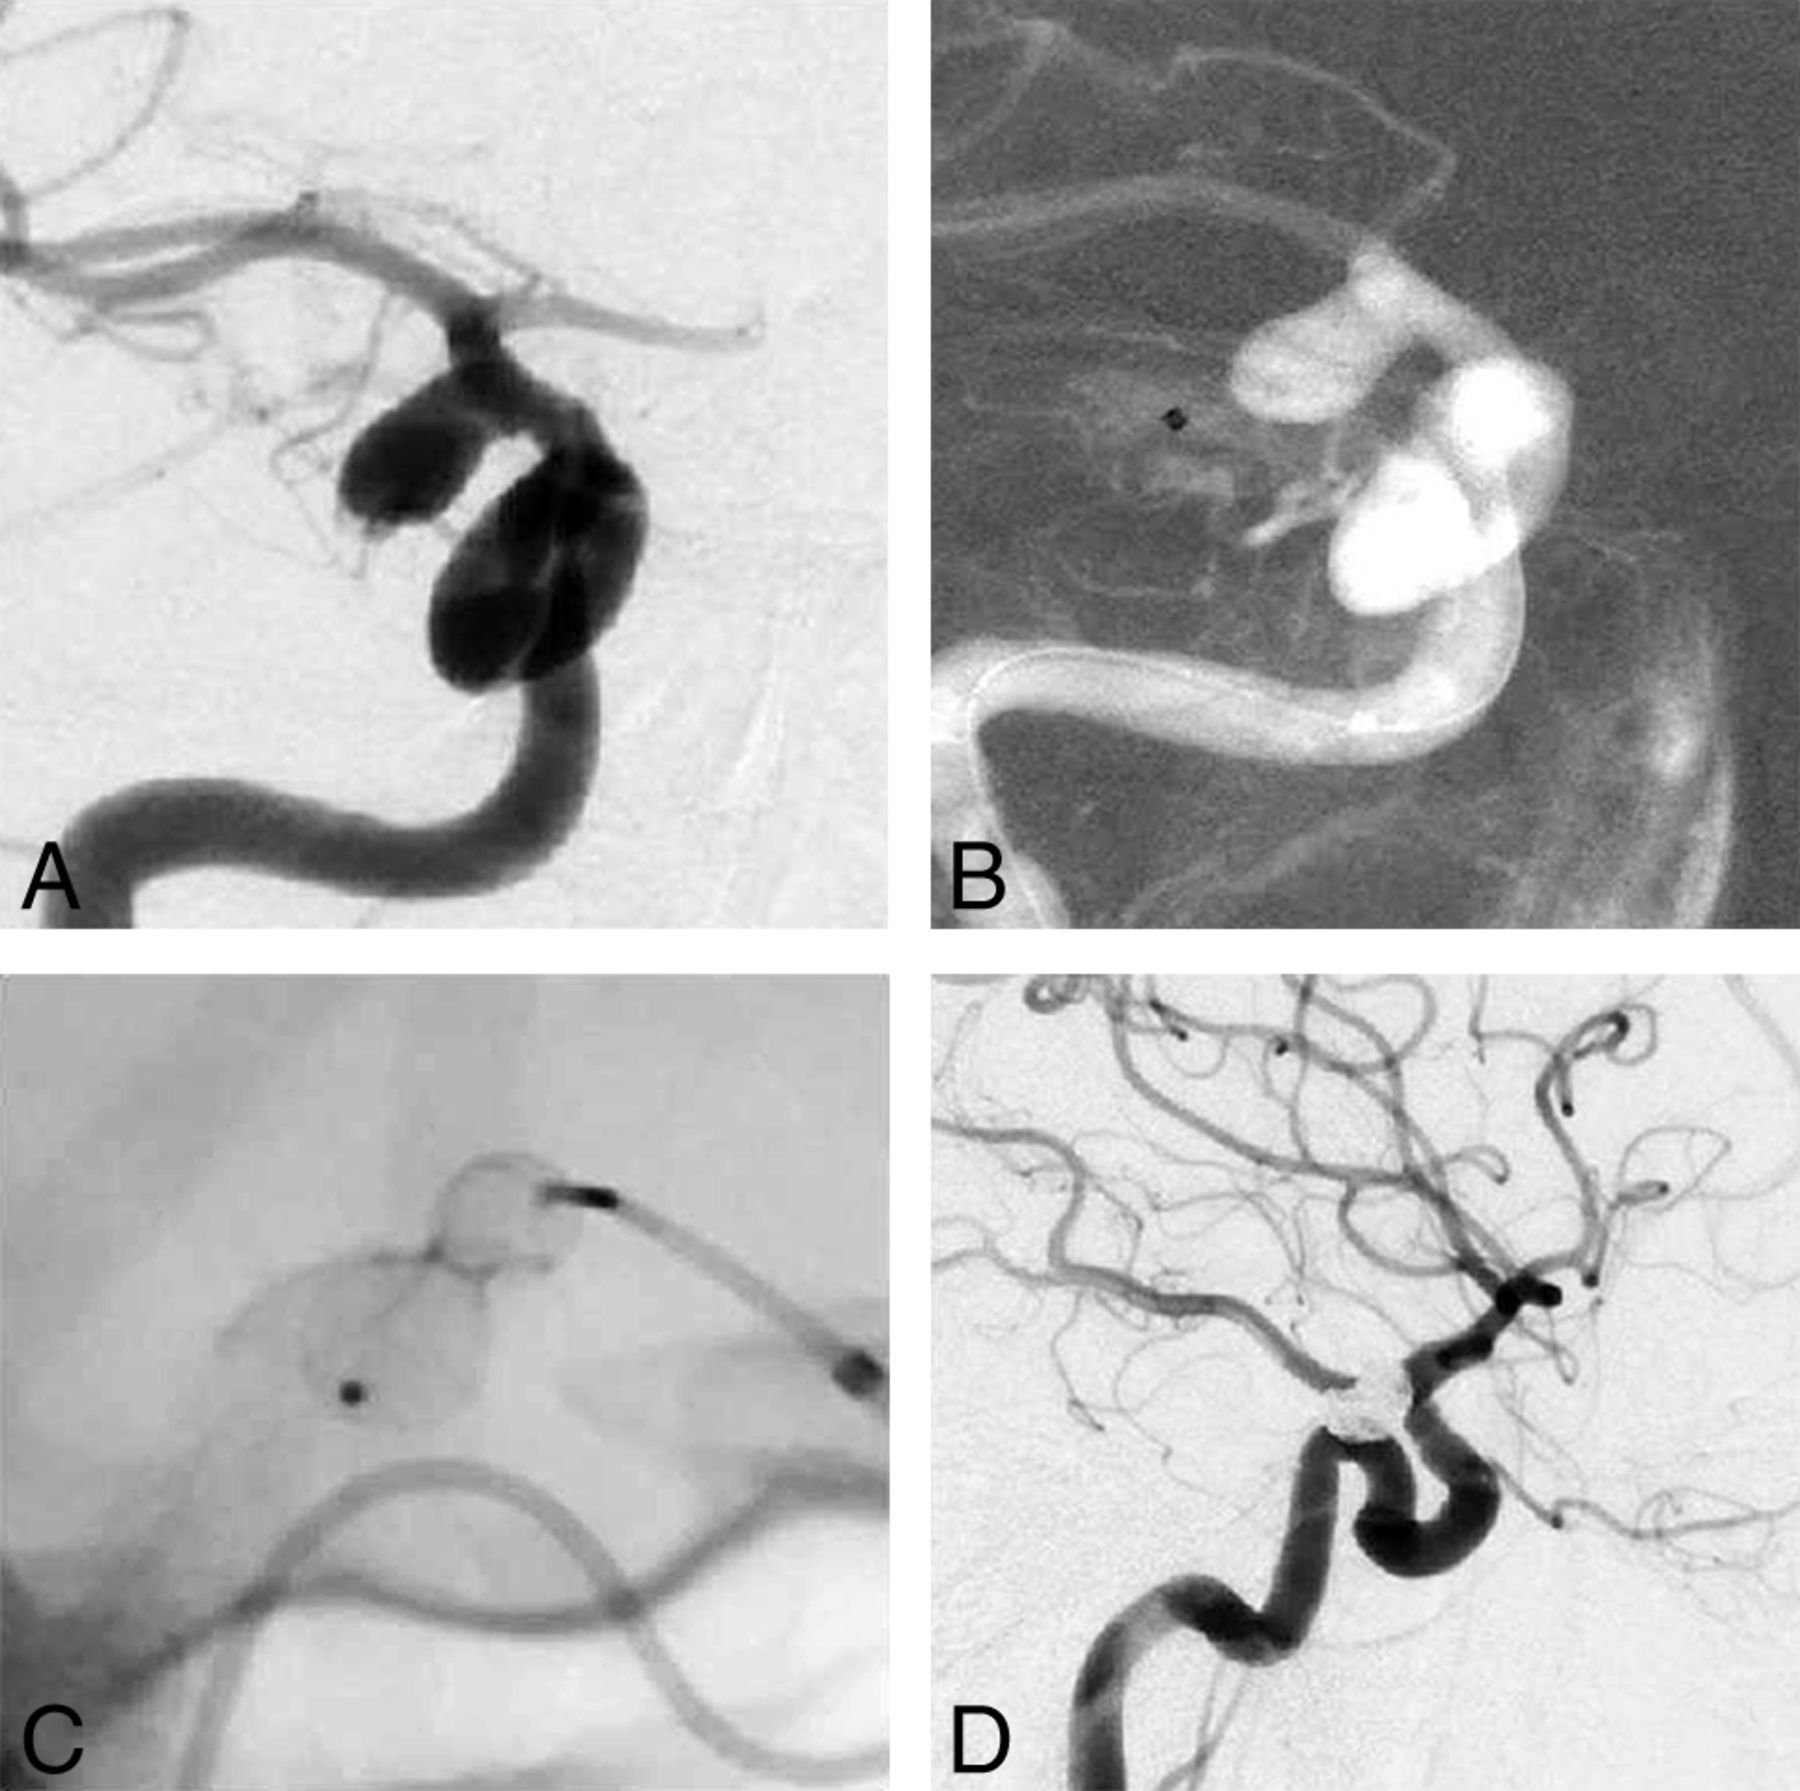

In 1 case of a ruptured ICA aneurysm, a rerupture occurred with a VIA 27 microcatheter. The microcatheter was left in place followed by the implantation of a WEB (SL 8 × 6) partially outside the aneurysm, which resulted in prompt hemostasis. The remaining aneurysm was then occluded by stent-assisted coiling (Neuroform Atlas). A left-sided hemiparesis resolved completely (Fig 2A–D).

A, Acutely ruptured broad-based ICA posterior communicating artery aneurysm (anteroposterior view). B, Catheterization followed by aneurysm rupture; VIA 27 microcatheter outside the aneurysm (roadmap in the anteroposterior view). C, Placement of a WEB SL 8–6 partly outside the aneurysm showing a constriction of the WEB at the point of rupture (single image without subtraction). D, Final complete occlusion of the aneurysm by stent-assisted coiling (lateral view).